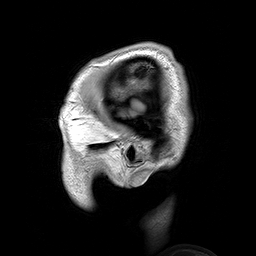

Small-angle X-ray scattering

(SAXS)

with my

MILLION DOLLAR BABY